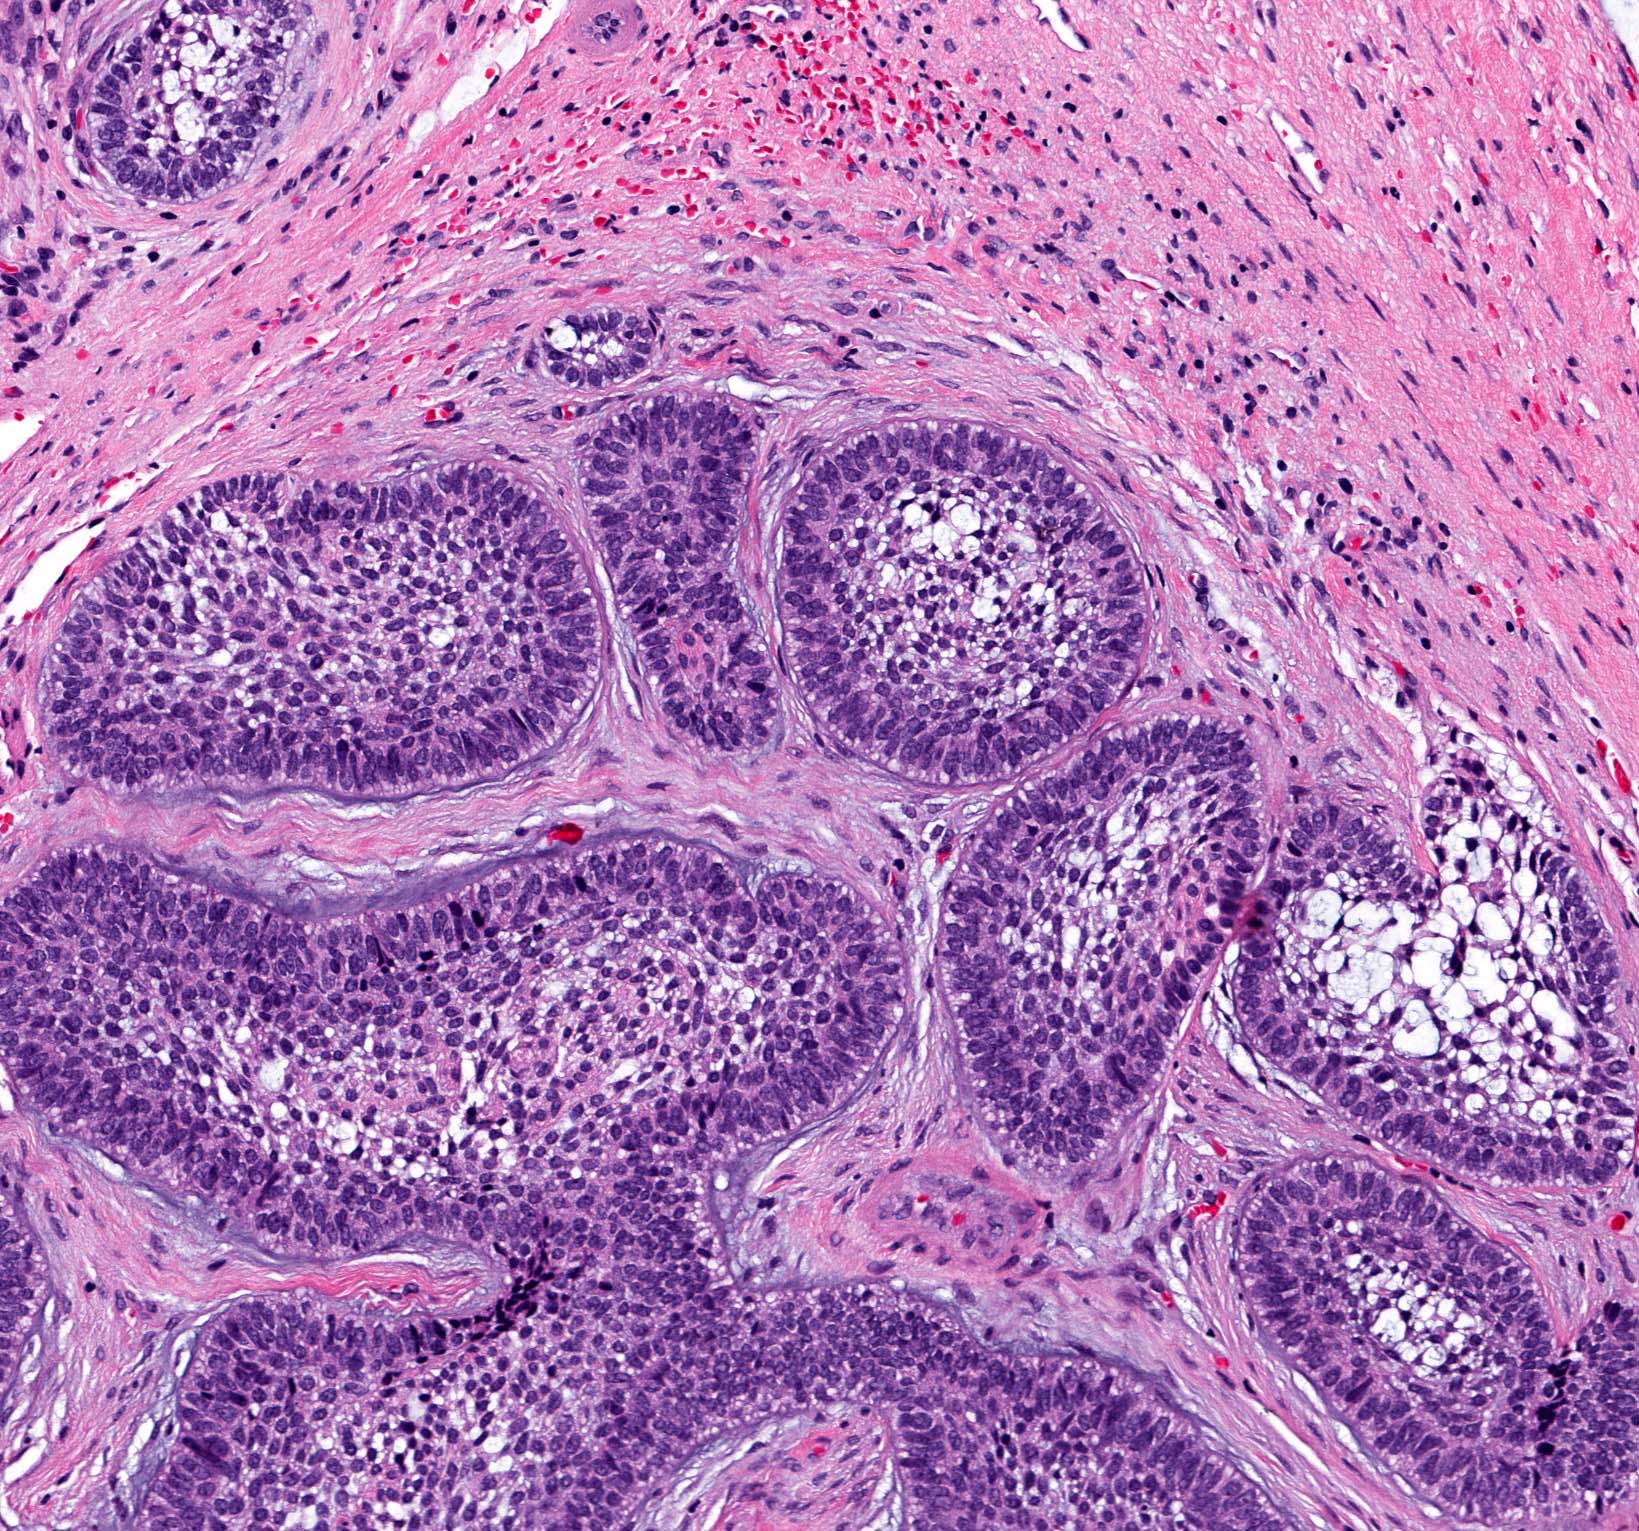

Microscopic (histologic) description

- Within the epithelial islands and cords of conventional ameloblastoma and the cystic epithelial lining of unicystic ameloblastoma, the odontogenic epithelium shows similar changes:

- Columnar cells with hyperchromatic nuclei at basal layer, exhibiting peripheral palisading

- Cells show reverse polarization away from basement membrane (Vickers-Gorlin change)

- Subnuclear vacuolization

- Suprabasal cells with a loose, network-like arrangement, recapitulating stellate reticulum formation seen in normal odontogenesis

- No dentin or enamel formation

- Ameloblastoma, conventional type has at least 6 histopathological patterns

- Single patterns may predominate within a given lesion, often mixed with 1 or more patterns

- Microscopic pattern has no documented prognostic significance

- Follicular: most common subtype; islands of odontogenic epithelium in fibrous connective tissue; may be cystic; classic peripheral palisading and stellate reticulum-like areas

- Plexiform: cords and sheets of anastomosing odontogenic epithelial cells; classic peripheral palisading and reverse polarity not always obvious

Contributed by Kelly Magliocca, D.D.S., M.P.H. and Anne C. McLean-Holden, D.M.D., M.S.